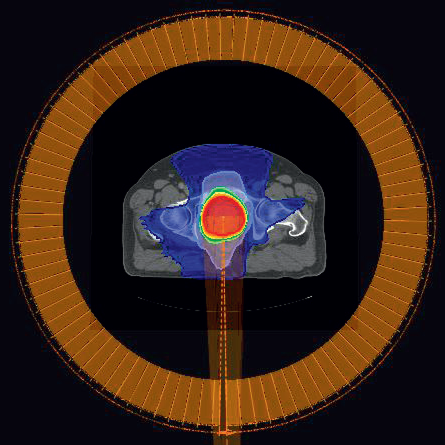

Figure 1

Figure 1: VDR plan for prostate patient P1. The orange bars around the patient indicates the MU delivered from the different directions. For the VDR plan, the MU per gantry angle varies. The total MU is 491MU and the delivery time is 68 seconds.